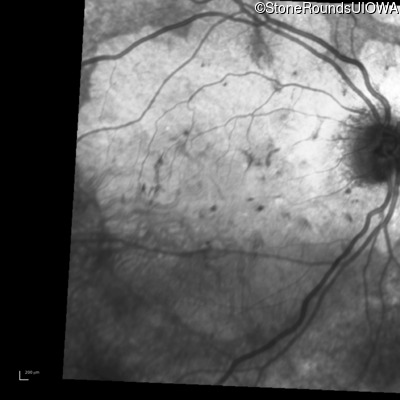

Foveal Hypoplasia (IIIG)

Diagnosis & molecular findings

Disease Gene Allele 1 variant(s) Allele 2 variant(s) Inheritance mode

Foveal Hypoplasia PAX6 Pro76Leu CCG>CTG   AD